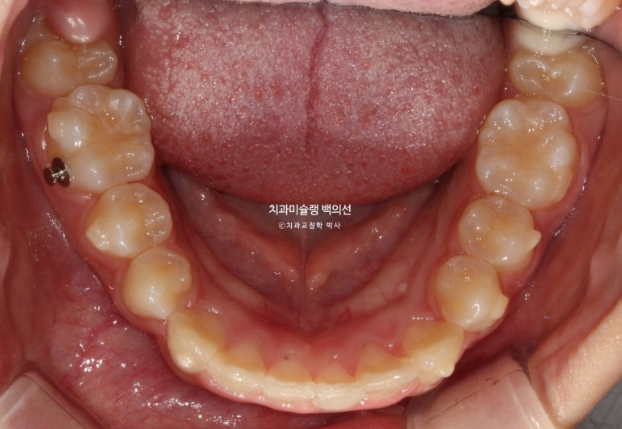

25.04

중심선은 정확하게 맞으며 과개교합이 잘 해소되었습니다.

어금니 교합은 물샐틈 없는 1급입니다.

유지장치까지 들어간 모습입니다.

총 치료기간은 1년 2개월, 재제작은 1회 했습니다.